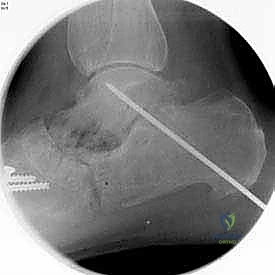

3. التصوير الشعاعي (X-rays): صور أشعة سينية أثناء الوقوف (Weight-bearing) لتقييم زوايا العظام ودرجة انهيار المفاصل.

بعد التأكد من الوضعية المثالية للعظام، يتم تثبيتها بقوة باستخدام مسامير معدنية مجوفة من التيتانيوم (Cannulated Screws) أو شرائح معدنية خاصة. يتم إدخال المسامير تحت توجيه الأشعة السينية المباشرة (Fluoroscopy) داخل غرفة العمليات لضمان الدقة المتناهية. هذه المسامير تضغط العظام معاً وتمنع أي حركة حتى يحدث الالتئام التام.